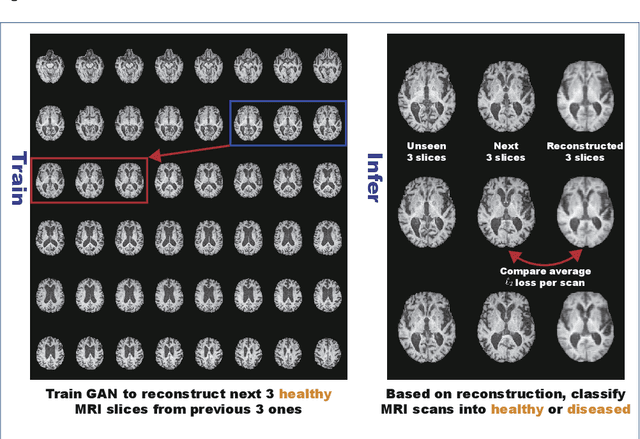

Abstract:Unsupervised learning can discover various unseen diseases, relying on large-scale unannotated medical images of healthy subjects. Towards this, unsupervised methods reconstruct a 2D/3D single medical image to detect outliers either in the learned feature space or from high reconstruction loss. However, without considering continuity between multiple adjacent slices, they cannot directly discriminate diseases composed of the accumulation of subtle anatomical anomalies, such as Alzheimer's Disease (AD). Moreover, no study has shown how unsupervised anomaly detection is associated with either disease stages, various (i.e., more than two types of) diseases, or multi-sequence Magnetic Resonance Imaging (MRI) scans. Therefore, we propose unsupervised Medical Anomaly Detection Generative Adversarial Network (MADGAN), a novel two-step method using GAN-based multiple adjacent brain MRI slice reconstruction to detect various diseases at different stages on multi-sequence structural MRI: (Reconstruction) Wasserstein loss with Gradient Penalty + 100 L1 loss-trained on 3 healthy brain axial MRI slices to reconstruct the next 3 ones-reconstructs unseen healthy/abnormal scans; (Diagnosis) Average L2 loss per scan discriminates them, comparing the ground truth/reconstructed slices. For training, we use 1,133 healthy T1-weighted (T1) and 135 healthy contrast-enhanced T1 (T1c) brain MRI scans. Our Self-Attention MADGAN can detect AD on T1 scans at a very early stage, Mild Cognitive Impairment (MCI), with Area Under the Curve (AUC) 0.727, and AD at a late stage with AUC 0.894, while detecting brain metastases on T1c scans with AUC 0.921.